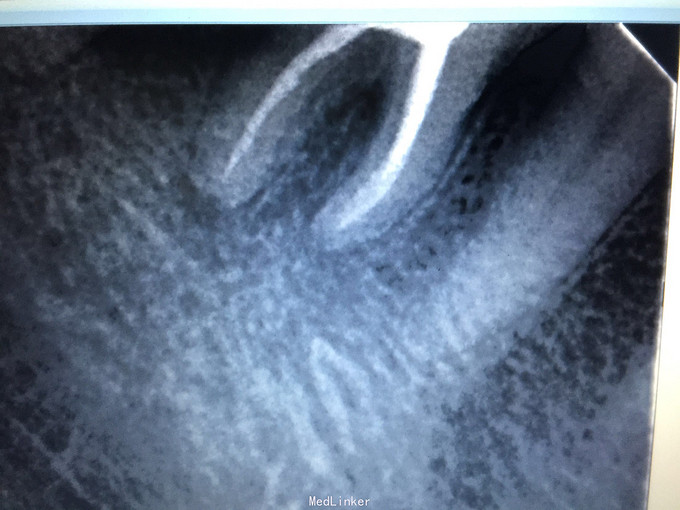

检查:46牙合面重度磨耗近髓,叩诊(+-),松动无,牙龈无明显红肿,冷诊(++)。 X线示:46牙合面缺损近髓腔,根尖无明显低密度影像。

诊断:46急性牙髓炎 治疗:46局麻下开髓揭顶全,慢失活,暂封,肿痛随诊。 二诊:46去暂封及失活剂,根管长度测量,根管预备,冲洗,干燥,根管消毒,根充,适充,锌基,树脂充填,调合,抛光,告医嘱。 建议46冠修复。

谈论:临床中许多磨耗明显的患牙,常以牙髓炎及根尖周炎症状表现出来,临床中此类牙常规根管治疗后,冠修复恢复牙体外形及咬合关系很重要。长期不修复,导致面下1/3距离缩短,影响美观及颞下颌关节功能。